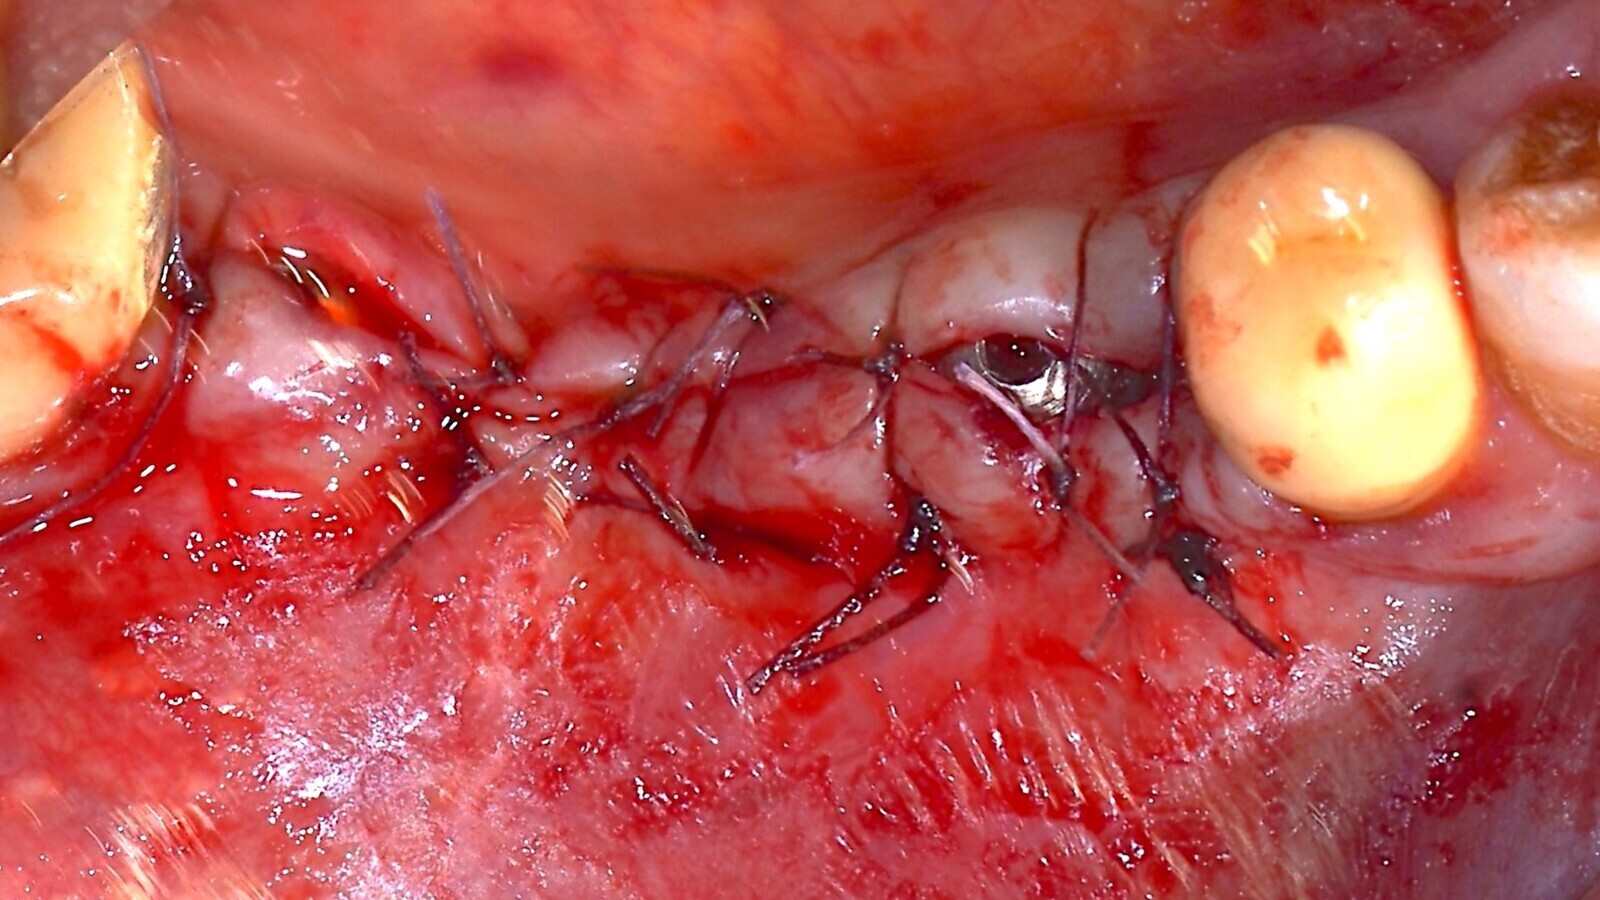

Los colgajos se cerraron con suturas Vycril 5-0 para favorecer la cicatrización de primera intención (Figs.7 y 8).

Fig. 7. Pasivación del colgajo para permitir el cierre de primera intención. Obsérvese la inserción de la tercera clavija estabilizadora de la lámina cortical flexible.

Fig. 8. Cierre del colgajo y cicatrización por primera intención.